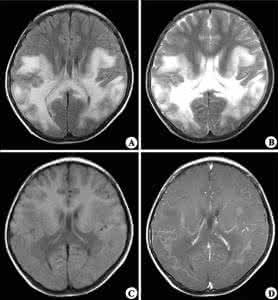

颅脑CT主要表现为脑室周围低密度影,颅脑MRI表现为T2加权像高信号影。脑干听觉诱发电位的检测可作为一个敏感、客观的指标发现脑干功能受累情况及亚临床病灶,为早期诊断脑白质疏松症的手段之一。